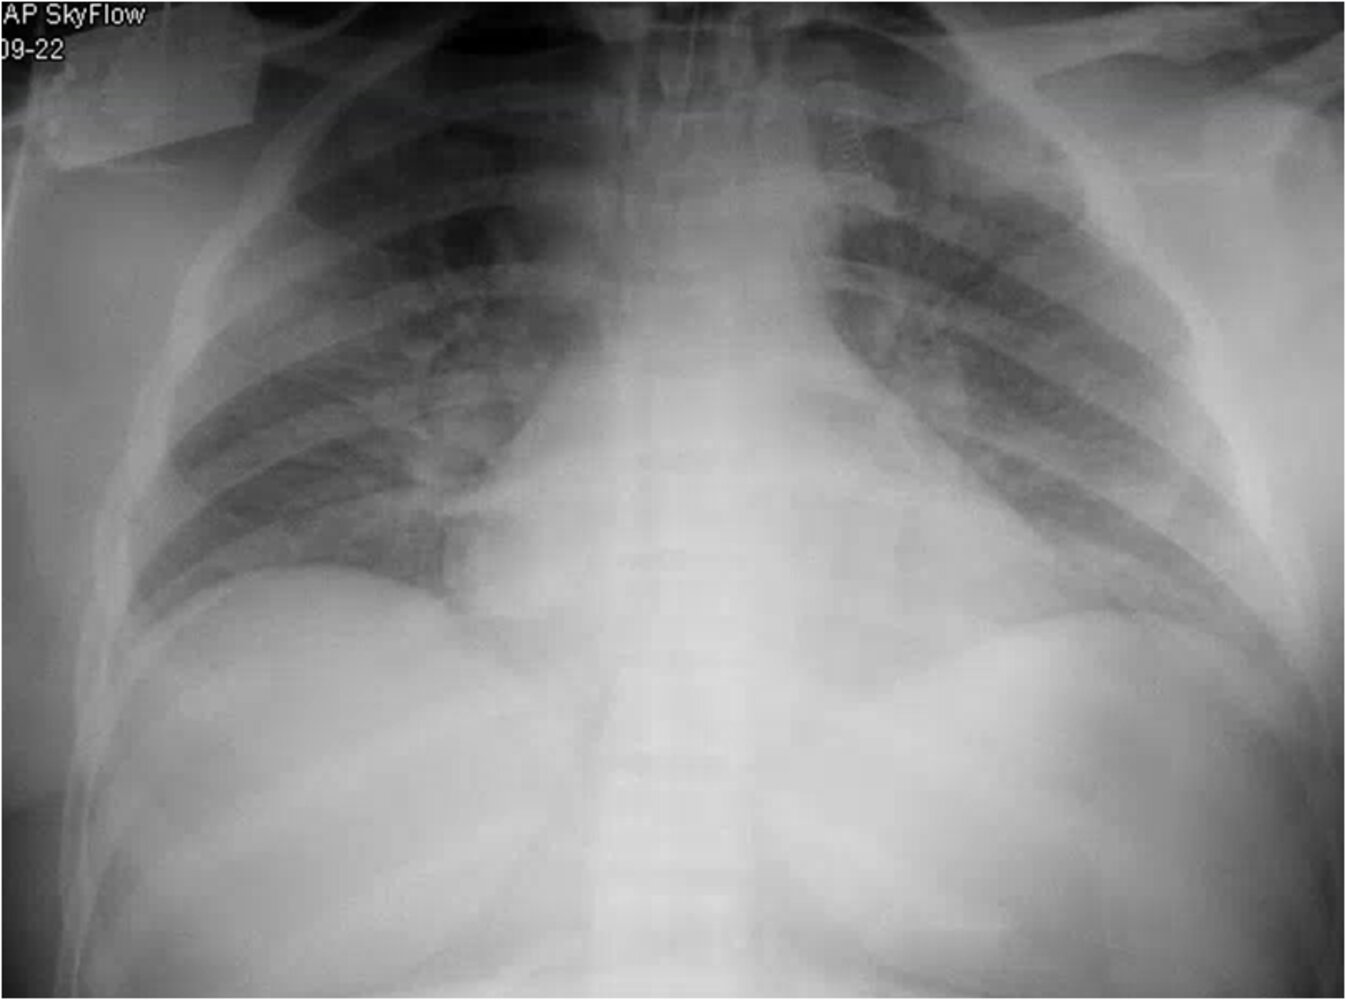

Imaging

• Chest x-ray

• Indication: all patients suspected of having ACS

• Supportive findings:

• New pulmonary infiltrate

• Segmental, lobar, or multilobular consolidation with or without the presence of pleural effusion

• If CXR is normal, it should be repeated in 24–48 hours if there is ongoing clinical suspicion for ACS. [6]